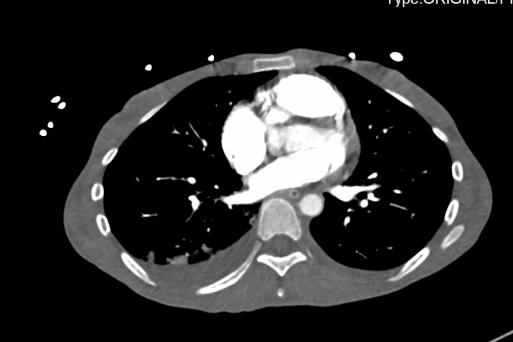

2021-4-29 CTPA:肺动脉干、左右肺动脉及其分支未见狭窄及明显充盈缺损。右肺、左肺下叶见斑片影、磨玻璃影及实变影。

2021-4-29全腹增强CT:腹盆腔散在积液,上腹腔少量积气,腹壁软组织积气,盆腔置管影。肝实质灌注不均,肝内淋巴瘀滞,提示肝功能损害。右侧见一支副肾动脉;左肾动脉提前分支。双侧附件区见多房囊状低密度影,可见环状强化,囊肿?卵泡?或其它?

2021-4-30心脏彩超:右心稍大,三尖瓣少-中量反流,估测肺动脉收缩压约74mmHg。

患者青年女性,慢性病程;主要表现为腹胀、呼吸困难,术后出现意识障碍、II型呼吸衰竭。经呼吸机辅助呼吸、对症支持等治疗后,患者意识恢复但呼吸困难无明显改善;既往有有粉尘接触史。查体见患者极度消瘦、营养不良,双肺呼吸音粗,可闻及散在湿啰音。血气示II型呼吸衰竭、高碳酸血症,轻度贫血,低蛋白血症,电解质紊乱,炎症指标、肌酶、BNP升高,院外腹水检查示漏出液,未见肿瘤细胞;胸部CT:双肺斑片影,抗感染治疗后病灶吸收;腹部增强CT:双侧附件区分别混杂密度团块影,内见多发囊泡影;心脏彩超:右心稍大,重度肺动脉高压。